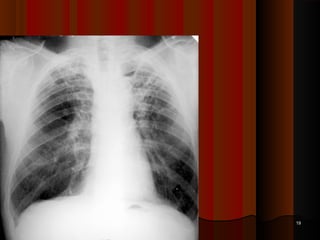

Secondary TuberculosisSecondary Tuberculosis

It is due to reactivation or reinfection of old, possibly subclinicalIt is due to reactivation or reinfection of old, possibly subclinical

infection.infection.

Site -Site -

 Apex of one or both lung,Apex of one or both lung,

 Histologically, there is chronic granulomatous inflammation withHistologically, there is chronic granulomatous inflammation with

caseous necrosis is present.caseous necrosis is present.

 The lesion may progress to a large confluent area of consolidation,The lesion may progress to a large confluent area of consolidation,

ultimately resulting into large fibrocalcific scar.ultimately resulting into large fibrocalcific scar.